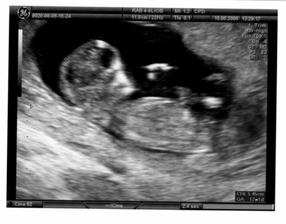

Ve středu 20.8.08 byla maminka s tatínkem v kině na muzikálu Mamma mia a já (malé miminko) jsem pařilo v bříšku až do rána. A na další den jsem se fotilo u pana doktora, ale o tom nic nevím, protože jsem po tak náročné noci celý den spinkalo. Alespoň si mě mohli pěkně vyfotit na 3D ultrazvuku. Změřili mi hlavičku a prý jsem se tatínkovi poved i když mě dělal po tmě

🙂.

Zatím mám takových 22 - 24 cm a vážím okolo 800 g.

Do obrazu se mi vejde už jen hlavinka.